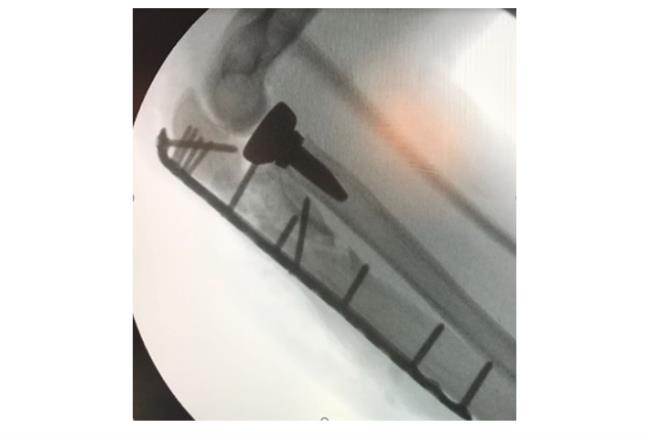

הניתוחים לאיחוי שברים מורכבים מתבצעים בשני שלבים: בשלב הראשון אם קיימות פציעות מורכבות או טראומה קשה מאוד, נפנה לטיפולים מצילי חיים. כמו כן, טרם ביצוע הניתוח יש לבחון אם קיימות פגיעות ברקמות רכות, העצבים או כלי הדם הסובבים את העצם הפגועה. הניתוח עצמו כולל כאמור חיבור של חלקי העצם באמצעות לוחות וברגים לשם יצירת מפרק חדש. בסיום הפעולה יש לוודא שהמפרק יציב. יציבות הקיבוע חשובה על מנת למנוע קיבוע של האזור לאחר ביצוע הפעולה. בצורה זו אנו מאפשריםהפעלה מיידית של המפרק, ומבטיחיםתוצאה טובה יותר שלטווחי תנועה בעתיד.

קיבוע של שבר במרפק והחלפת ראש רדיוס | באדיבות פרופ' דורון נורמן